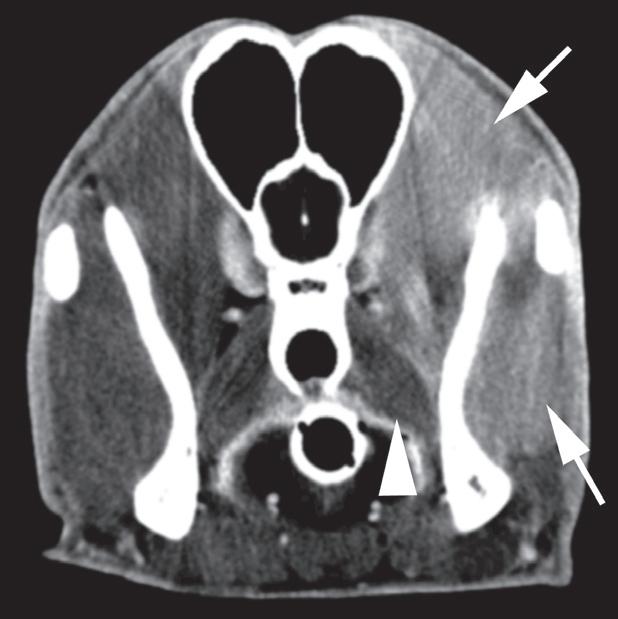

Rycina 1.4.5. Zapalenie mięśni żwaczy (pies) TK

Badanie wykonano u 1,5-rocznego, kastrowanego rottweilera z szybko postępującym brakiem możliwości otwierania pyska. Prezentowane obrazy TK wykonano bezpośrednio po podaniu środka kontrastowego. Widoczne jest umiarkowane, rozlane wzmocnienie pokontrastowe mięśni żwacza i skroniowego po lewej stronie (a, b – strzałki).

Wydaje się, że mięśnie skrzydłowe są niezmienione (a, b – grot strzałki).

Biopsja mięśni ujawniła rozlane, przewlekłe, limfoplazmocytarne zapalenie mięśni z zanikiem i włóknieniem